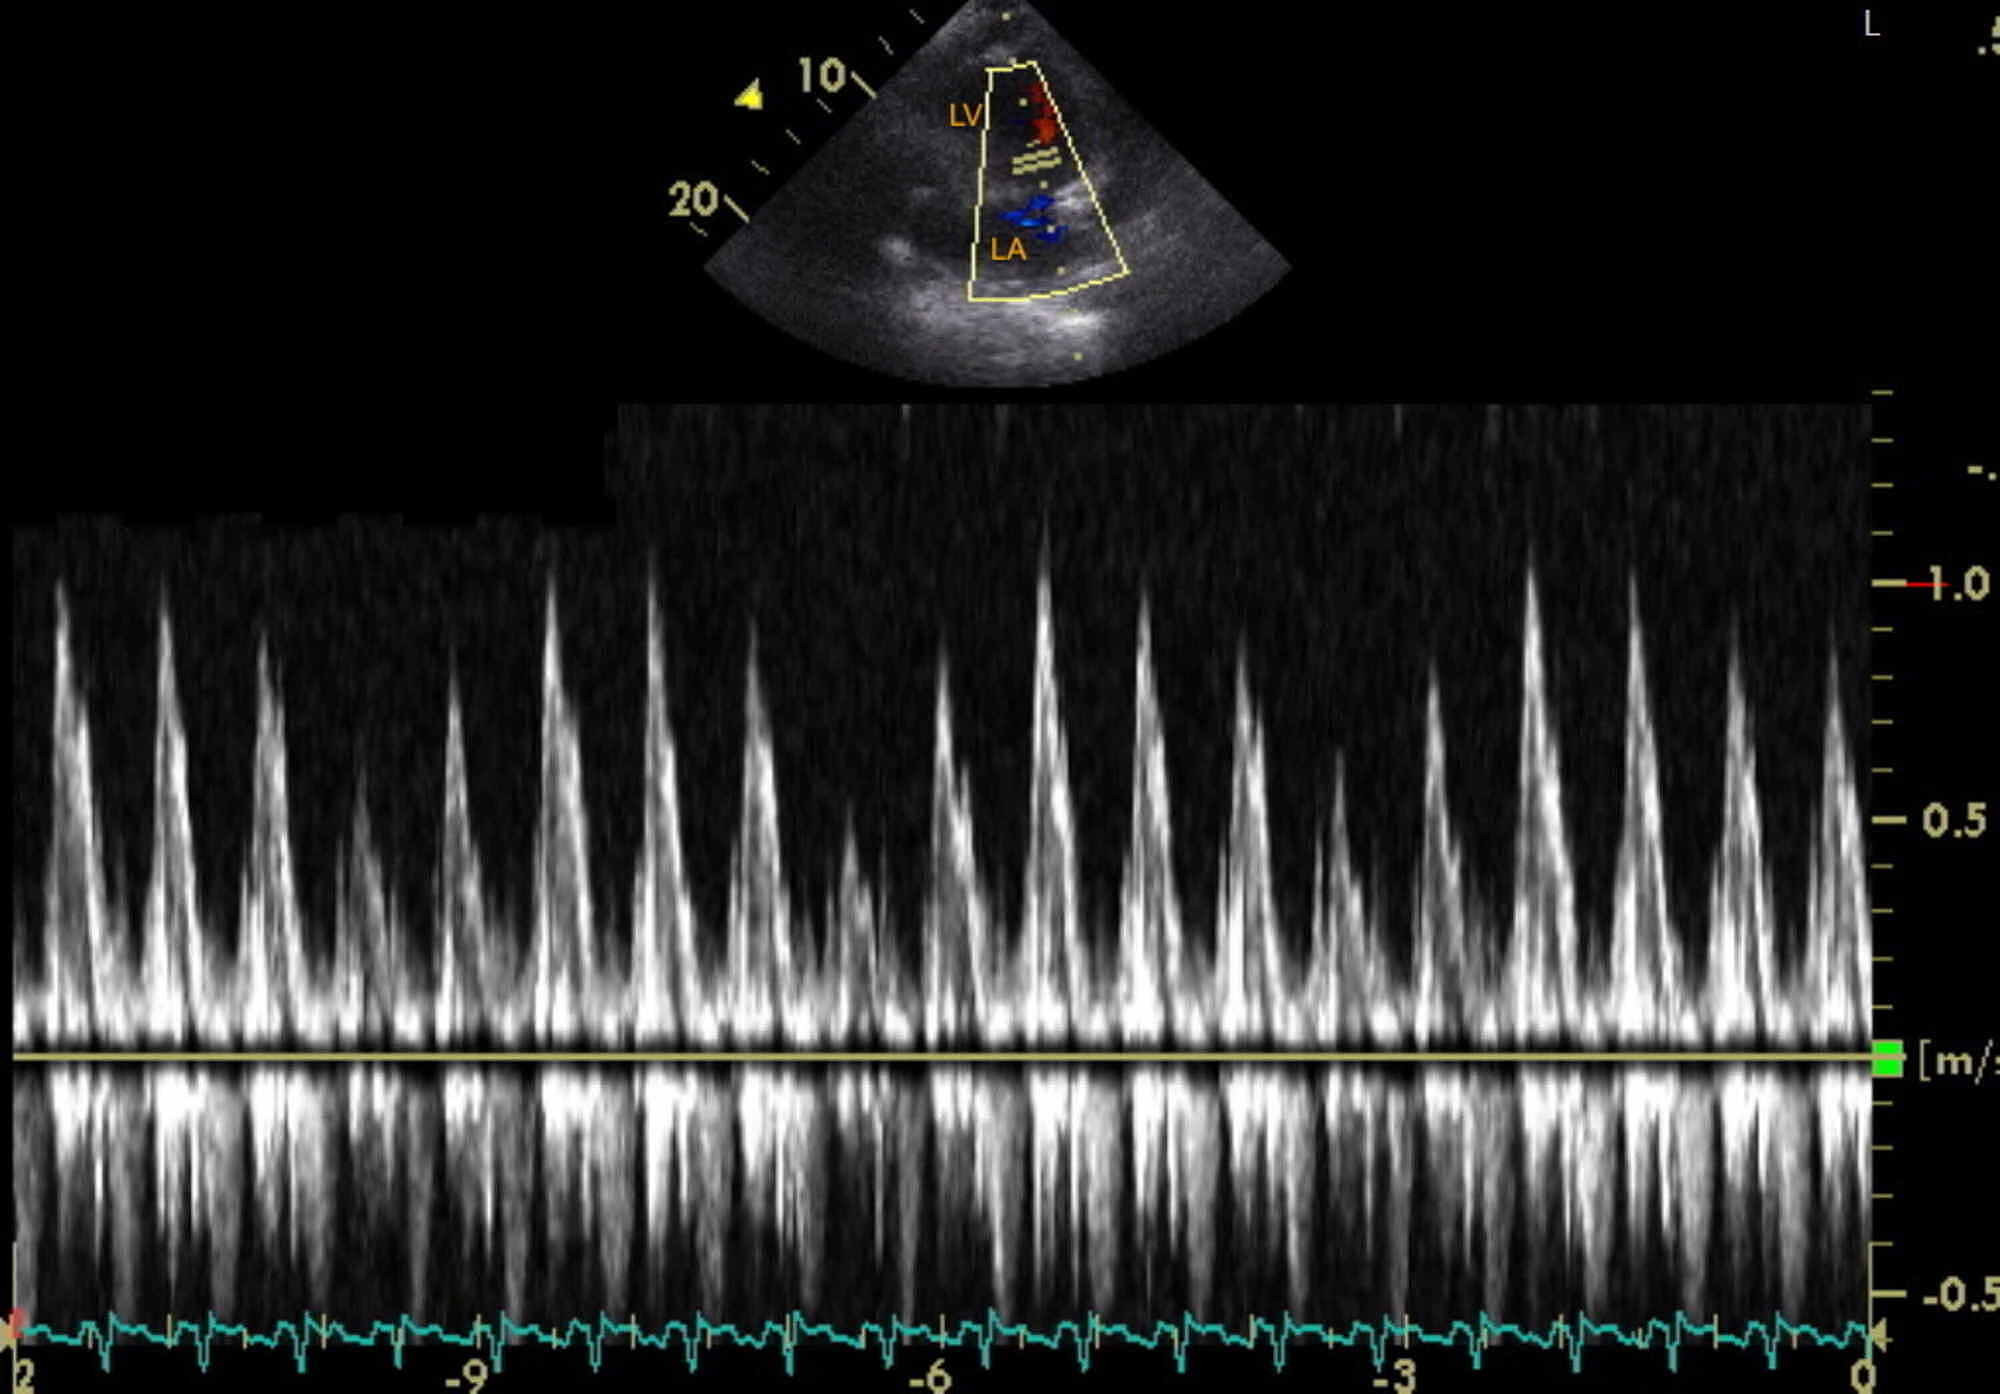

Transthoracic echocardiogram showing a mitral valve inflow E wave Tamponade Mitral Inflow Variation A pericardial effusion (larger size associated with tamponade), diastolic right. Web echocardiographic findings include: Echo signs • early signs: Web the pathophysiology of tamponade entails exaggerated variations in the normal haemodynamic changes that occur during respiration. » ivc dilated, not collapsing » increased respiratory variation in mitral (> 25%) and tricuspid (> 40%) inflows • late signs: Web (a) diagram. Tamponade Mitral Inflow Variation.

Tamponade Mitral Inflow Variation . Echo signs • early signs: Web echocardiographic findings include: » ivc dilated, not collapsing » increased respiratory variation in mitral (> 25%) and tricuspid (> 40%) inflows • late signs: A pericardial effusion (larger size associated with tamponade), diastolic right. Web several echocardiographic features support the hemodynamic diagnosis of tamponade, including early diastolic collapse of the right. Web (a) diagram showing mitral and tricuspid valves inflow patterns variability with the respiratory cycle in cardiac tamponade. Web the pathophysiology of tamponade entails exaggerated variations in the normal haemodynamic changes that occur during respiration.

Echo signs • early signs: Web the pathophysiology of tamponade entails exaggerated variations in the normal haemodynamic changes that occur during respiration. Web several echocardiographic features support the hemodynamic diagnosis of tamponade, including early diastolic collapse of the right. A pericardial effusion (larger size associated with tamponade), diastolic right. Web echocardiographic findings include: Web (a) diagram showing mitral and tricuspid valves inflow patterns variability with the respiratory cycle in cardiac tamponade. » ivc dilated, not collapsing » increased respiratory variation in mitral (> 25%) and tricuspid (> 40%) inflows • late signs: